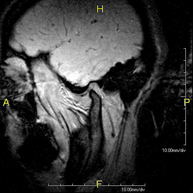

- Brain MRI (cranial)

This non-invasive diagnostic procedure uses an electromagnetic field and radio waves (from a transmitter and receiver) to acquire high-definition anatomical images of the brain. It is a radiation-free procedure. Indicated for: vascular problems, memory loss, epilepsy, headache, malformations, suspected tumour, meningitis.

- Cerebrospinal fluid (CSF) flow MRI

This non-invasive diagnostic procedure uses an electromagnetic field and radio waves (from a transmitter and receiver) to acquire high-definition anatomical images of the cerebral ventricular system. It is a radiation-free procedure. Indicated for: study of hydrocephalus and stenosis of the cerebral aqueduct.